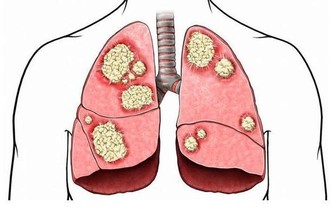

嘴角出現了口瘡,有可能是抵抗力薄弱引起,因此,需要補充足夠的維生素C。維生素C可以從水果,蔬菜中獲取,作為常見的水溶性維生素,營養價值比較高,獲取足夠的維生素C最明顯的效果就是提高抵抗力。

而在免疫功能增強時,身體對抗外來細菌,病毒入侵的能力都增強。這樣可以防止維生素C缺乏出現不良症狀,也是在改善嘴角長口瘡這種現象時需要補充的重要維生素。